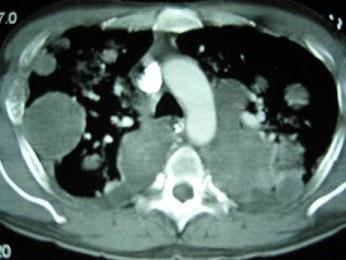

问题 33岁,男,咳嗽1周,有骨肉瘤病史,请结合胸片和CT选出最可能的诊断 ( )

选项 A、结节病 B、错构瘤 C、粟粒性肺结核 D、骨肉瘤转移 E、肺梗死

答案 D